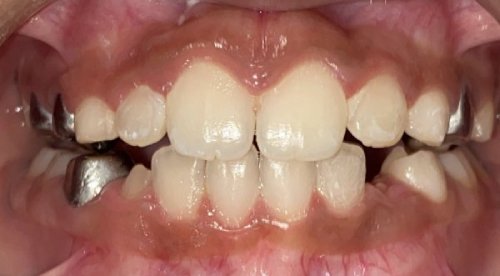

Actual Patient: Bailey

Img Before 3 1 Img After 3 1

Severe “Overbite”, BUCK TEETH, Narrow Jaws, Severe Deep Bite

Bailey Before 1 Beliy after img

Treatment Time:

7.5 months

Front View

Top View

Right & Left Sides